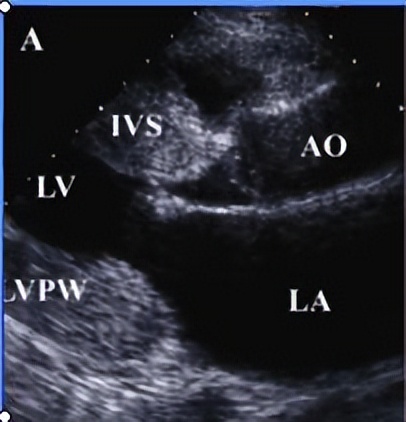

超声心动图

左心室明显扩大,左心室流出道扩张,室间隔及左室后壁搏动幅度减弱,二者搏动幅度之和 <13mm 。病变早期可有节段性运动减弱,二尖瓣前后叶搏动幅度减弱。二尖瓣开口小,二尖瓣叶可有轻度增厚。右心室及双心房均可扩大,心衰时,二尖瓣可呈 类城墙样 改变,心衰控制后恢复双峰。心脏彩超是扩张型心肌病临床诊断、判断预后、评价治疗的 最常用、最有价值 的方法。

四、扩张型心肌病心脏彩超检查有哪些异常

(1)全心扩大: 全心扩大,尤以 左心室扩大 最为明显。正常成年男性左室舒张末期内径(LV)< 55毫米 ,女性< 50毫米 ,而扩张型心肌病患者往往超过以上正常标准数值。

(2)左室形态改变: 正常左室形态呈 椭圆形 ,扩张型心肌病患者的左室明显扩大,呈 球形 改变。

(3)室壁运动弥漫性减弱: 扩张型心肌病患者的心脏室壁运动呈弥漫性减弱,部分亦可出现节段性运动异常。超声心动图检查提示扩心病的室壁运动幅度< 0.3厘米 ,室间隔增厚率< 15% 。

(4)射血分数减低: 扩张型心肌病患者的心脏收缩功能明显减低,收缩功能指标以左室射血分数(LVEF)最为敏感,正常人LVEF> 55~75% ,扩张型心肌病病人LVEF多< 50%

(5)二尖瓣开放幅度减低: 由于心脏泵血功能减低,左室舒张末期压力增高,二尖瓣开放受限而致舒张期开放幅度减低。

(6)三尖瓣关闭不全: 扩张型心肌病晚期右室受累或继发 肺动脉高压 ,以及二者所致的三尖瓣瓣环扩大,均可引起三尖瓣关闭不全。

(7)心室内血栓: 心腔内血栓较常见,多发生于左室心尖部,与心室收缩力降低、心室内 血流速度减慢、血液淤积 有关。